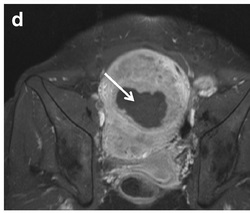

Standardizing analysis and reporting of MRI in patients with leiomyoma is important, given the extremely high prevalence and wide spectrum of treatment options. Nowadays, MRI is the pivotal examination for the work-up.

Article: European Society of Urogenital Radiology (ESUR) Guidelines: MR Imaging of Leiomyomas